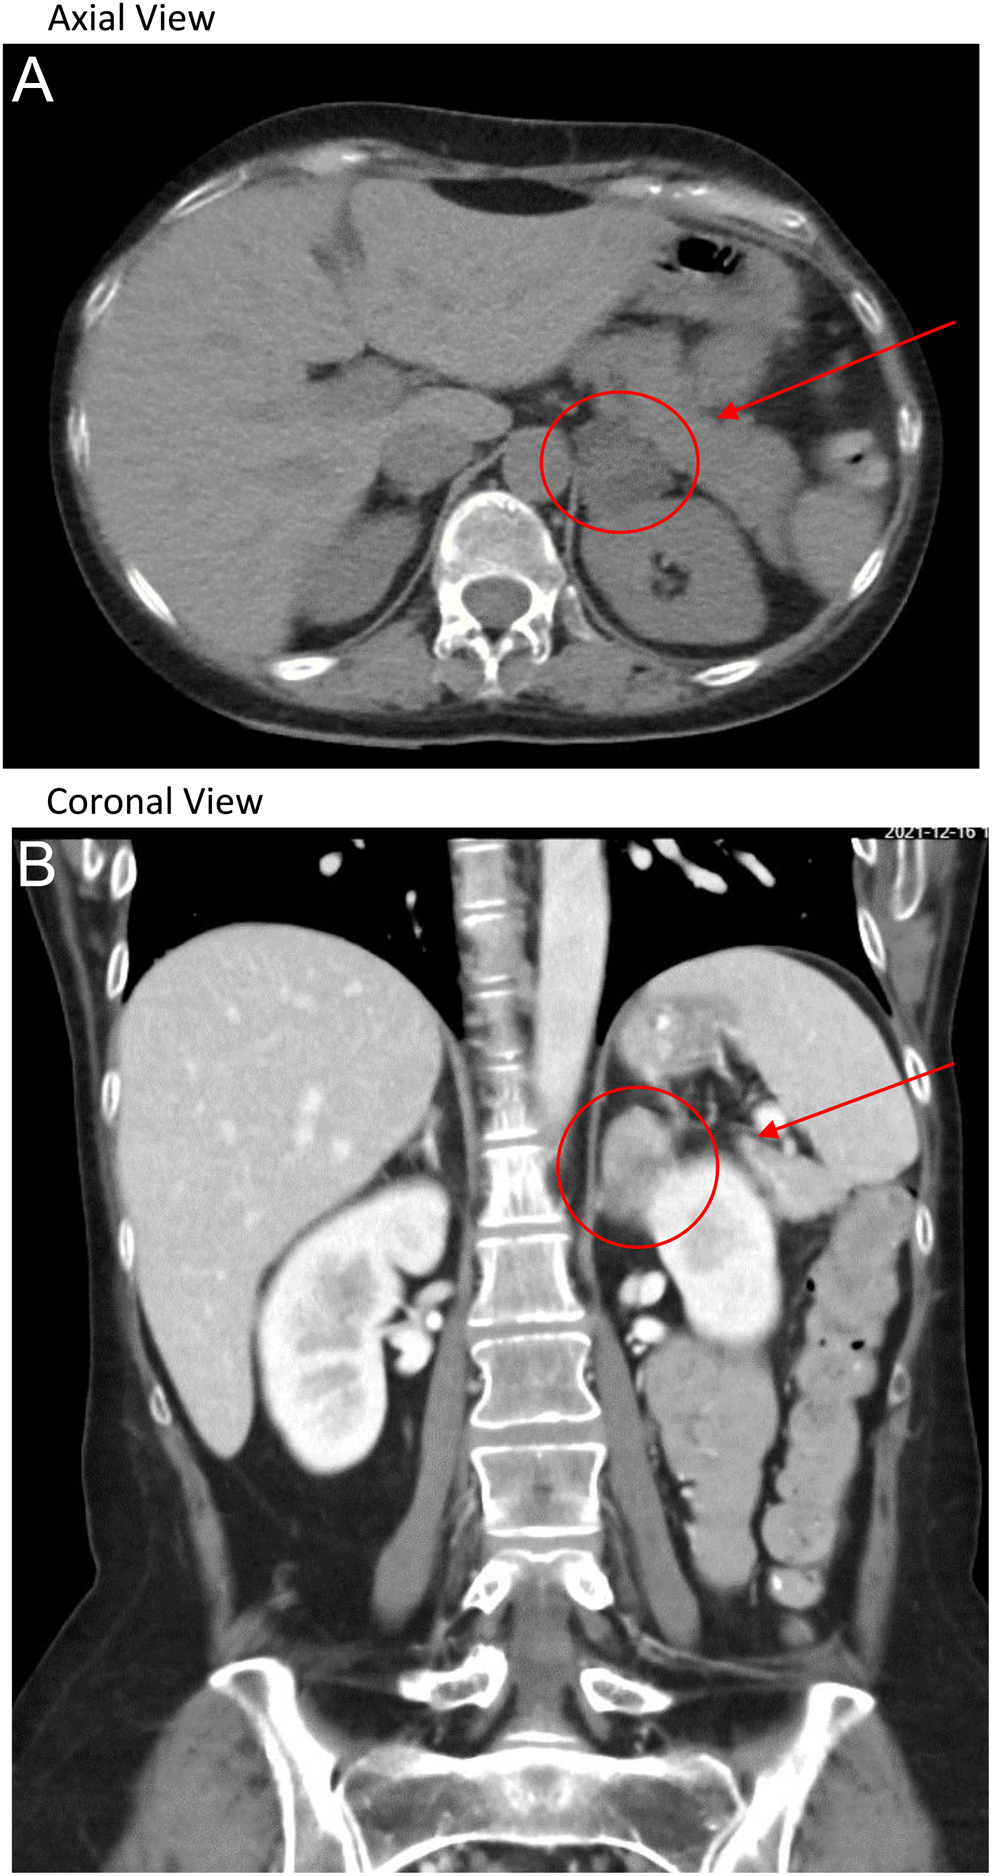

(PDF) ACTHindependent Cushing’s syndrome due to ectopic Cushing Syndrome Cause Amenorrhea Another pituitary cause of amenorrhea is cushing's syndrome, which results from prolonged exposure to glucocorticoids like cortisol and is. This dysfunction typically results from the effects of. Women may experience amenorrhea ( a complete lack of menses), or irregular periods. Hormone secretion by pituitary tumors in patient with cushing's disease or acromegaly can also cause amenorrhea. Our case involved amenorrhea. Cushing Syndrome Cause Amenorrhea.